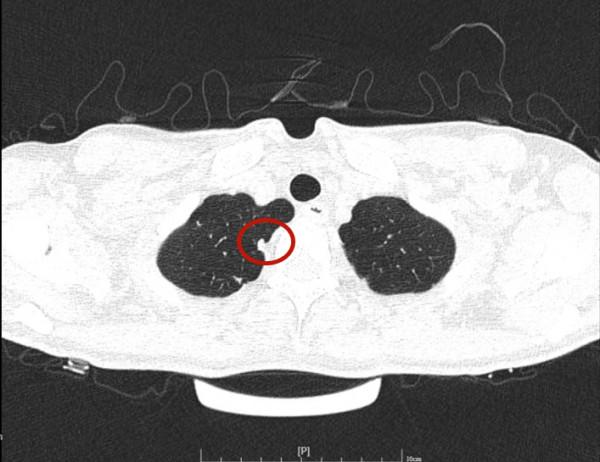

那麼多結節,基本上都是實性,分佈兩肺,形態不似圓形或類圓形的轉移瘤。是什麼呢?我們是不是一定要弄明白到底是什麼病?其實我覺得有時並不一定要弄清楚,所以我回復的意見如下:我認為我們看病,有時候可以從結果來反推,從而考慮是不是干預治療。比如這個病例的兩肺多髮結節,我看沒有一個是主病灶,也就是說“明顯考慮惡性的,其他考慮是這個病灶轉移的”這種樣子。那麼這些實性小結節,可能是:1、良性結節:包括慢性炎,纖維增生、肺內淋巴結、風溼結節、肉芽腫、隱球菌等各種可能性。但只要是良性,不處理不影響生命,也沒什麼不舒服,只需關注著,定期複查就可以了;2、腫瘤多發轉移:不管原發灶在哪裡,如果兩肺這麼多轉移,你再怎麼治療,預後也不好,現在還不是典型的腫瘤,也未見明顯的原發部位,遲點有進展再考慮又有多少區別呢?3、結核:即使真是結核,沒有明顯症狀的情況下,很多人自己得過結核也不自知,意思是說,如果痰找結核菌陰性,不是活動性肺結核,沒有症狀,不治療也沒什麼關係,也是隻需要定期複查。所以你的病例,我的意見是:1、形態數目不像惡性;2、不需深究到底是什麼;3、把診斷交給時間來決定,建議每4-6個月複查平掃,有變化時展再考慮活檢或干預,否則先不去管它。